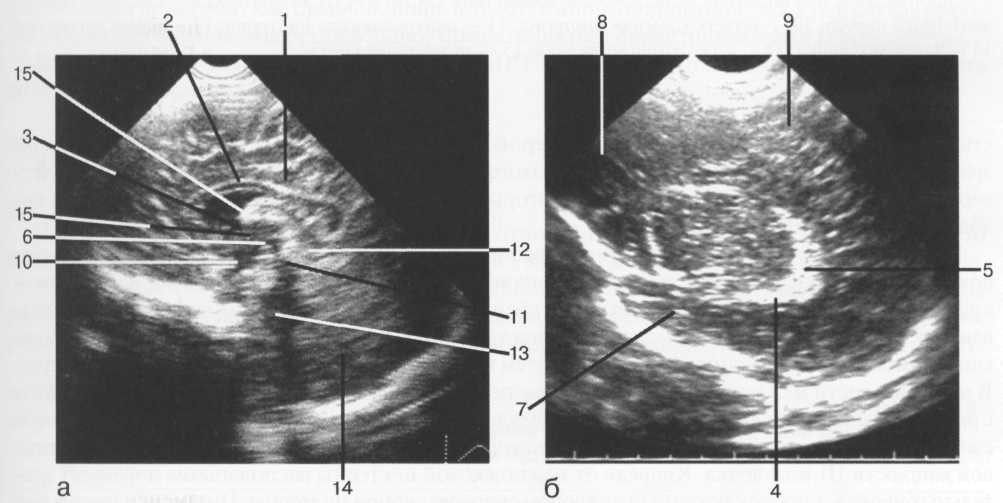

Ультразвуковое сканирование также может быть использовано для ис­следования головного мозга, но лишь в раннем детском возрасте, когда со­хранен родничок. Именно над мембраной родничка и располагают детек­тор ультразвуковой установки. У взрослых производят преимущественно одномерную эхографию (эхоэнцефалографию) для определения расположения срединных структур мозга, что необходимо при распознавании объемных процессов в мозге (рис. 42).

Рис. 42. Нейросонография. Изображения головного мозга в сагиттальной плоскости: а -- срединно-сагиттальный срез; б -- парасагиттальный срез через тела боковых желудочков.

I -- поясная борозда; 2 -- мозолистое тело; 3 -- межжелудочковое отверстие; 4 -- сосудистое сплетение нижнего рога; 5 -- клубок сосудистого сплетения; 6 -- III желудочек; 7 -- височная доля; 8 -- лобная доля; 9 -- теменная доля; 10 -- инфундибулярный карман; 11 -- водопровод среднего мозга; 12 -- четверохол-мная цистерна; 13 -- IV желудочек; 14 -- мозжечок; 15 -- межталамическая спайка.